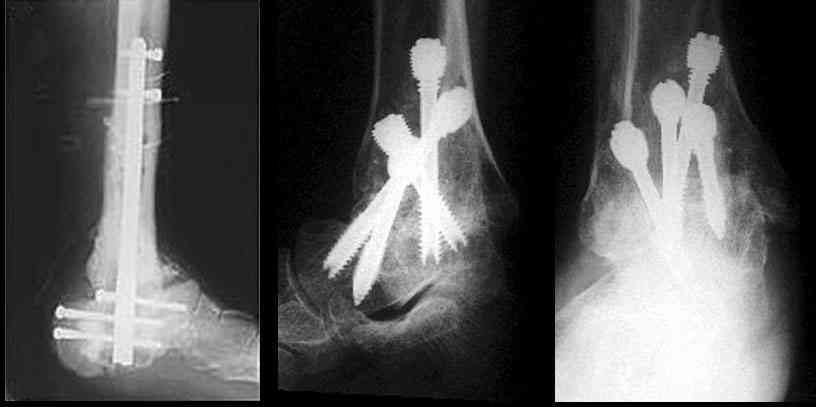

Существуют специальные системы для артродеза голеностопного сустава. См. приложение

Можно: 65-летняя пациентка, оперирована по поводу несросшегося в гипсе перелома лодыжек с патологической вальгусной установкой стопы и выраженным нарушением опрной функции. Оперирована через 6 месяцев после травмы. Рентгенограммы через 4 месяца после операции.

Уважаемый А.Семенистый. Складывается впечатление, что вы выполнили трехсуставный артродез, уж больно длинные блокирующие винты. Не мешают ли они пациентке при ходьбе?

Да конечно винты длинноваты! Мешают ли ходить? Во всяком случае субьективно пациентка удовлетворена. Ходит, естевственно, хуже чеи до травмы, но намного лучше, чем до операции.